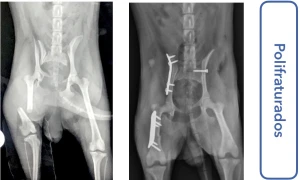

Sou médico veterinário especializado em ortopedia e cirurgias complexas em cães, com atuação em Ribeirão Preto. Realizo procedimentos como cirurgia de ligamento cruzado (TPLO), correção de luxação de patela e tratamento de fraturas, sempre com foco na recuperação funcional e qualidade de vida do paciente.

• Cirurgia de joelho, patela e fraturas em cães